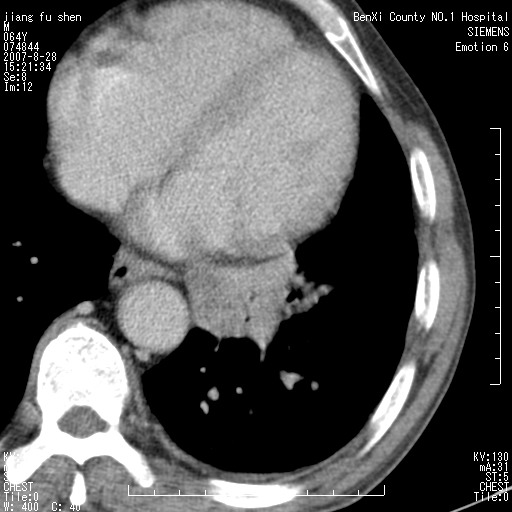

男、64、咳嗽、发烧一周、左肺呼吸音稍弱。既往肺结核,右手结核。

本次扫描患者未带原片,左肺下叶发现病灶。左肺上叶空洞,5组淋巴结肿大,1cm左右。

平扫20-33hu

增强31-33hu

1分半44-52

2分55-67

考虑左肺中央型肺癌并阻塞性肺炎

考虑左肺中央型肺癌并阻塞性肺炎,建议纤支镜检查